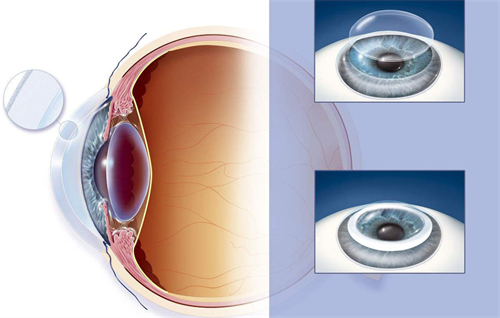

在白内障手术技术迭代浪潮中,艾无极人工晶体凭借“一术多效”的连续视程技术,成为中高端患者群体的热门选择。

作为强生眼力健基于TECNIS平台研发的第三代无级变焦晶体,它突破传统单焦点、多焦点晶体的局限,通过创新光学设计实现远中近视力无缝衔接,同时覆盖近视、散光、老花眼矫正需求。

单次手术同步解决白内障、近视、散光、老花眼四大问题,术后脱镜率较高。

晶体材料抗撕裂性提升,术后晶体移位风险降低,适合角膜条件复杂或瞳孔较大的患者。